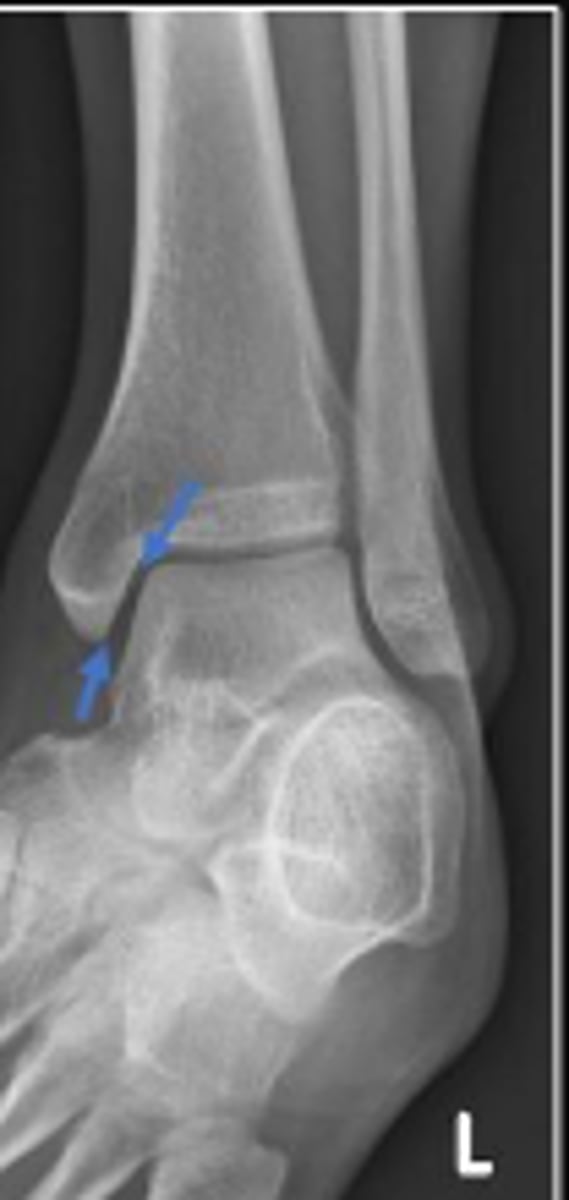

Left internal oblique ankle

What is the name of the radiographic view?

Left distal tibia

What bone are the arrows pointing to?

Left distal fibula